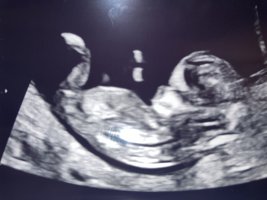

Legger også ved en potty shot, for gøy!

ikke så vi noe nub heller